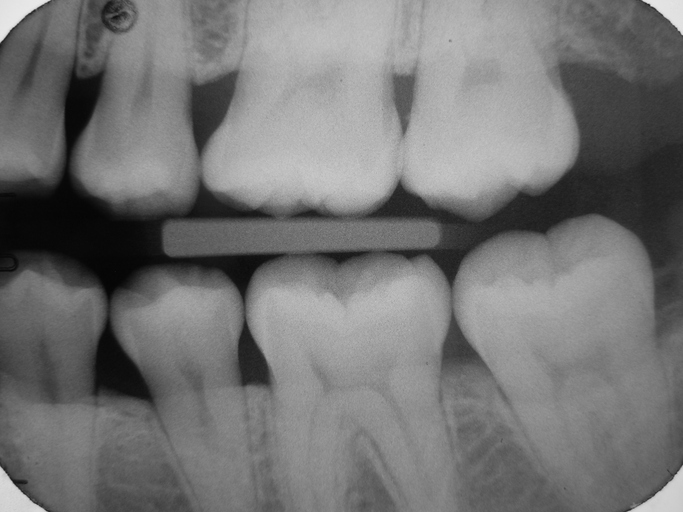

Plain radiography more frequent imaging modality over CT for maxillofacial trauma

Clinicians may commonly use a less favorable type of imaging when performing the initial examination of patients with maxillofacial trauma.

In a retrospective study published in JAMA Network Open, investigators used administrative claims data from the Merative MarketScan Commercial Claims and Encounters Database to analyze the use of plain radiography versus guideline-concordant computed tomography among a group of more than 280,000 adult patients presenting with maxillofacial trauma between 2013 and 2022. They stressed that plain radiography often provides limited diagnostic value in these types of injuries.

The investigators discovered that more than one-quarter of the patients involved in the study received plain radiography during initial imaging; however, the use of plain radiography declined from nearly 33% to 18% by the end of the study period.